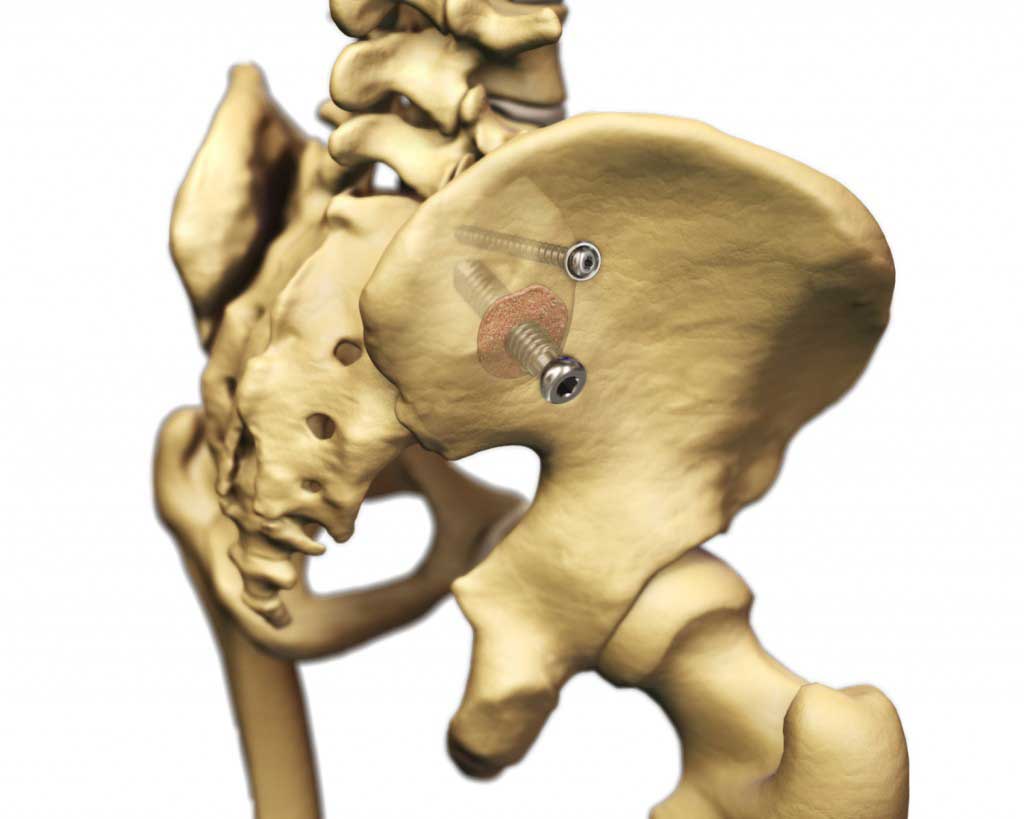

For all my website subscribers and readers, I offer you my new page on the Zyga SImmetry® – True SI Joint Arthrodesis (fusion) surgical option for Sacroiliac Joint Instability/Dysfunction (SIJD) and Pathology. I cannot not personally recommend this procedure as I do not have direct experience with it; however, as a fusion alternative to my Stryker Cannulated Screw Fixation without fusion procedure done for my diagnosis code: 724.6-Disorders of the Sacrum , I do recommend this product for those that need a fusion over screw fixation only. I do have the permission of my Northwest Zyga Representative to use their content here on my website and I feel honored to do so. (Click on images to enlarge)For more in depth information on this surgical procedure, here is a Dove Press Journal on Medical Devices: Evidence and Research published article authored by Larry E. Miller and Jon E. Block entitled:

Minimally invasive arthrodesis for chronic sacroiliac joint dysfunction using the SImmetry SI Joint Fusion system